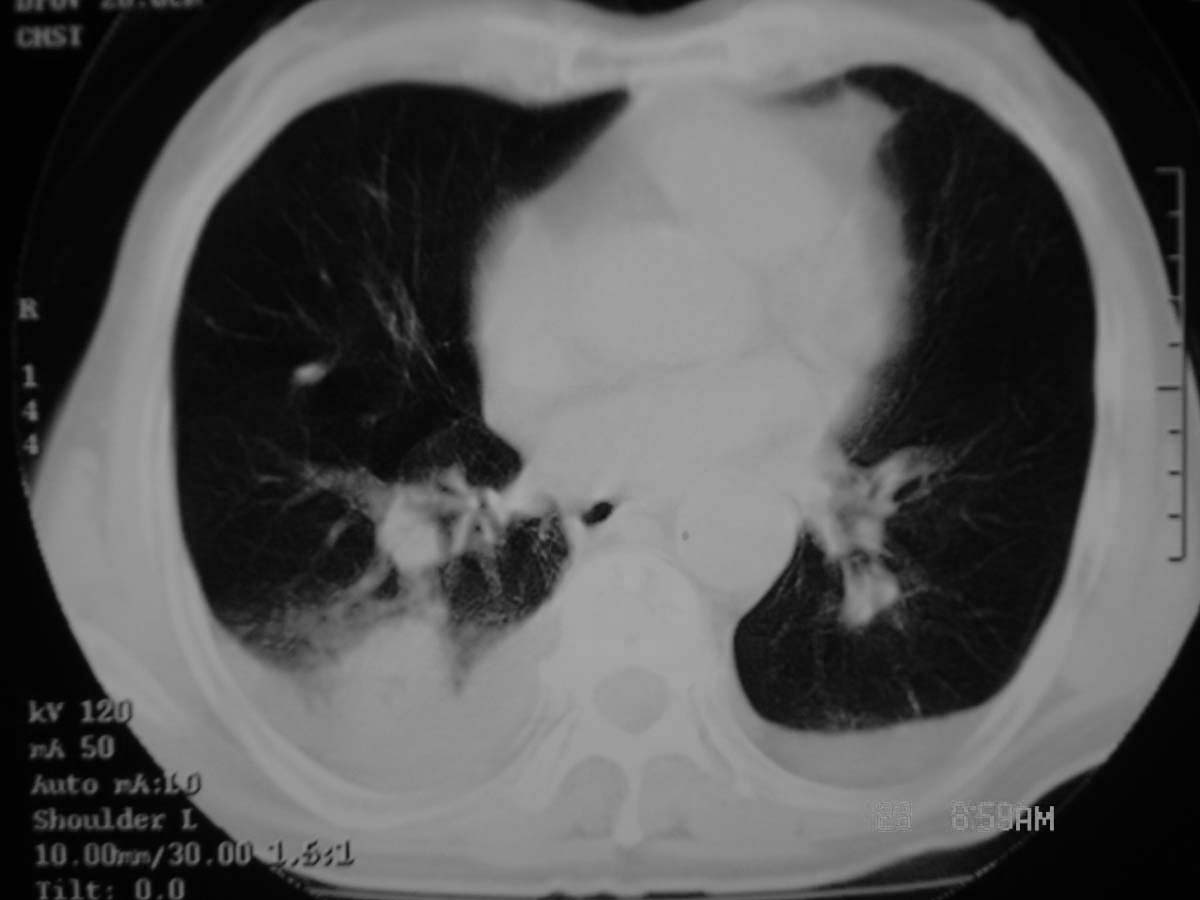

以下是引用守望可可西里在2006-11-23 14:33:00的发言:[br][br] 糖尿病病人很容易继发结核,病人又有双侧胸膜增厚、粘连、胸腔积液以及双上肺的斑片状、条索状影结核病灶影,以一元论考虑,右下肺病变首先考虑干酪性肺炎,可以正规抗炎治疗后复查,排除一般的肺炎。